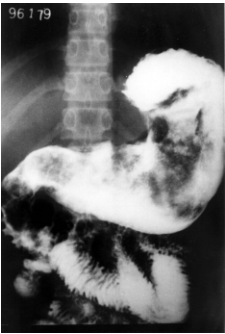

Analise o seguinte exame contrastado do estômago, realizado em uma paciente com queixas de dor hipogástrica há 2

meses.

Com base no exposto anteriormente, é correto afirmar que o exame